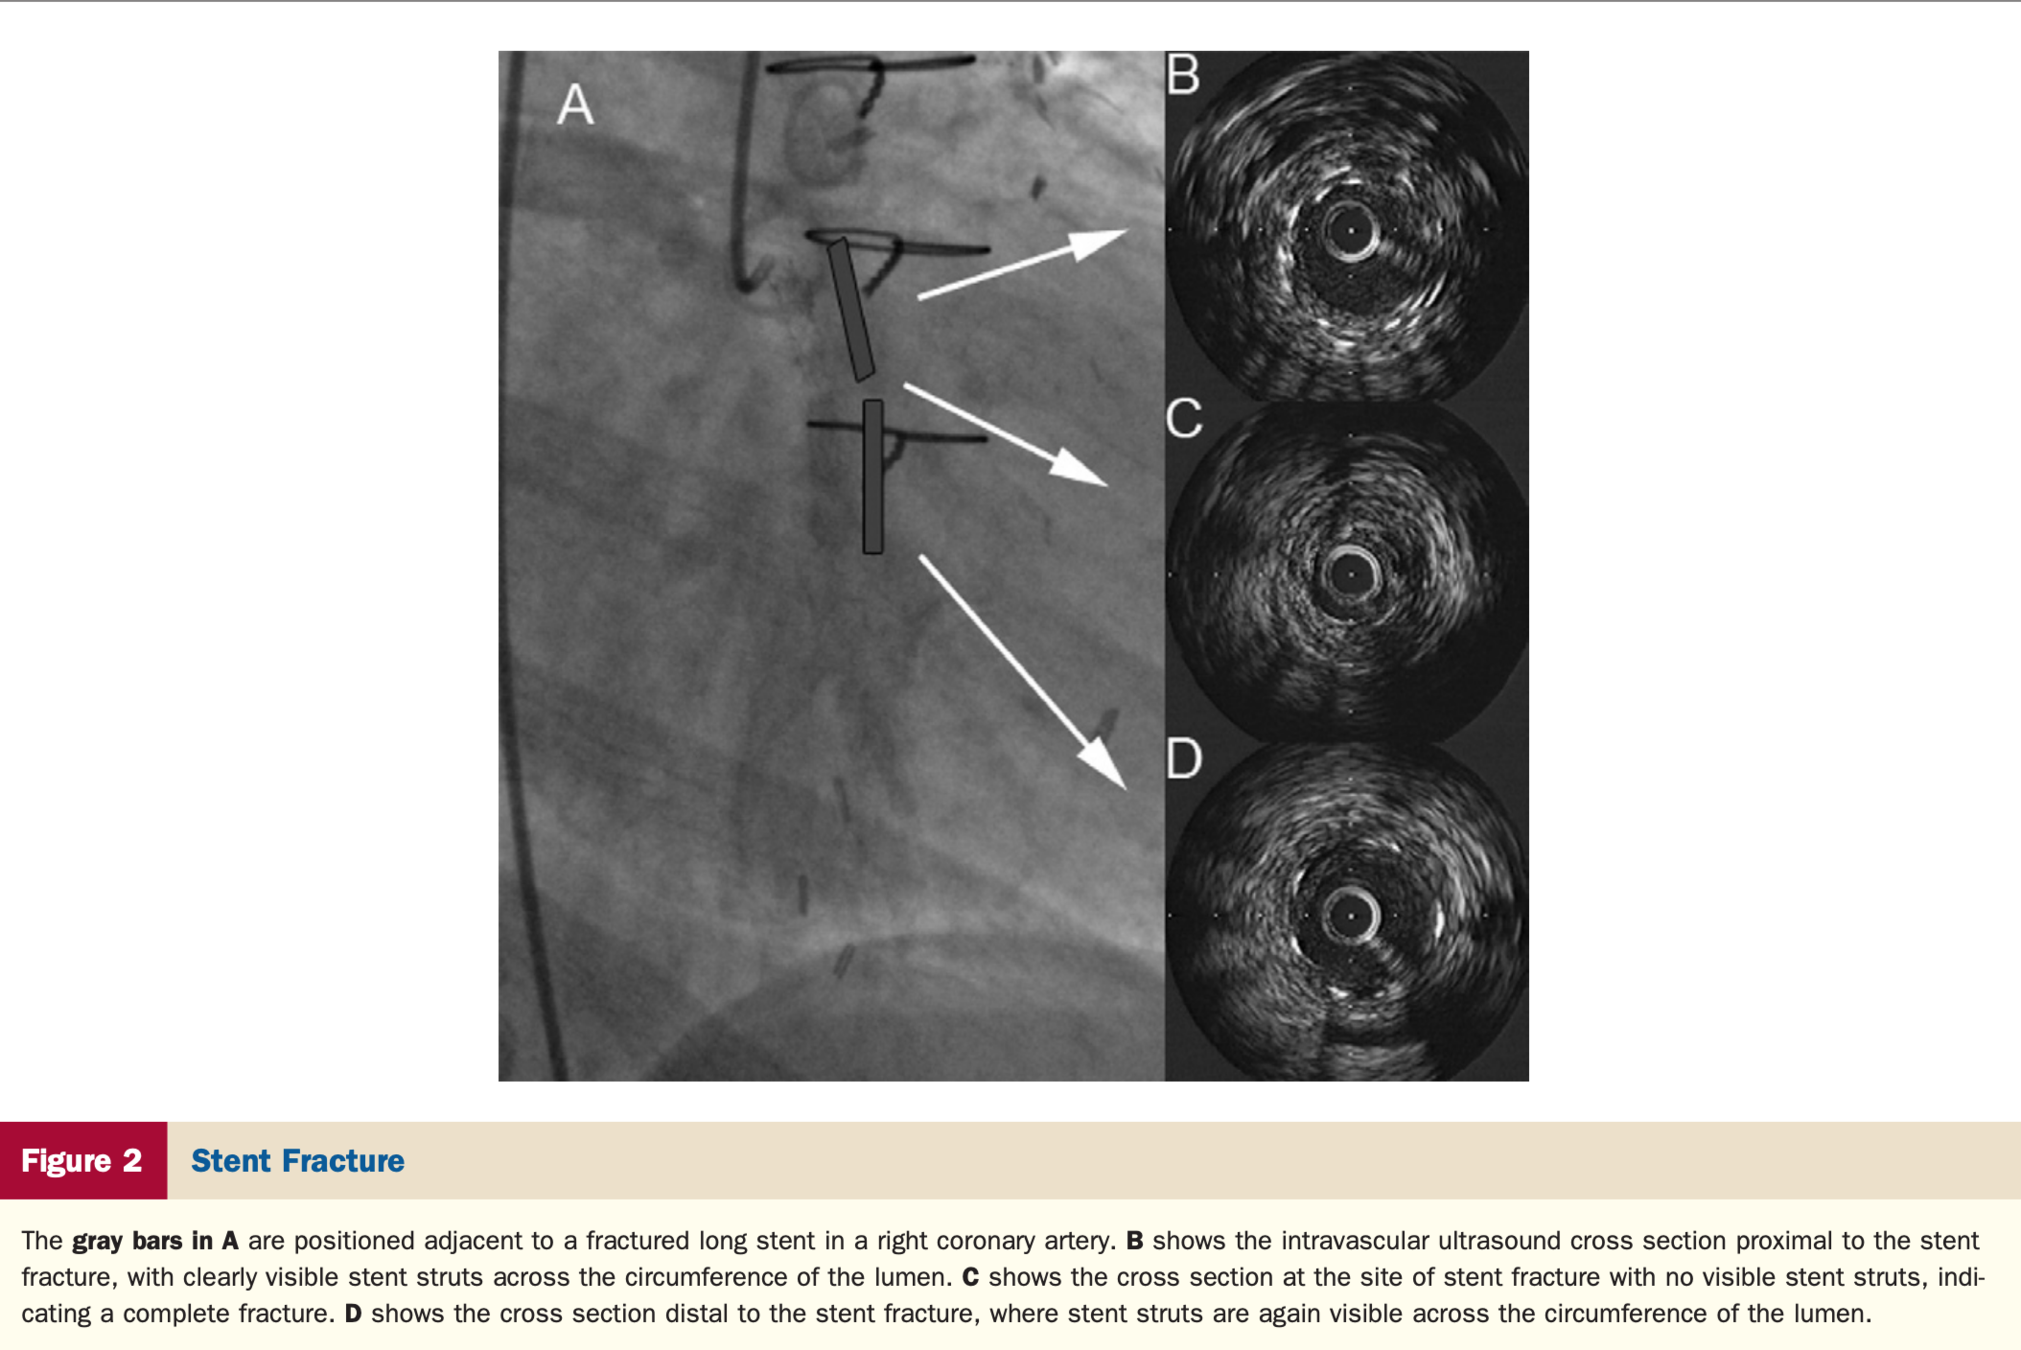

In patients with stent failure, IVUS or OCT is reasonable to determine the mechanism of stent failure (Class IIa).

• "Assessment  of  the  cause  of  stent  thrombosis  with  intracoronary  imaging  is  important to guide subsequent treatment. Similarly, advanced  imaging  techniques  have  an  important  role in detecting underlying mechanical and pathophysiological  factors  that  contribute  to  in-stent  restenosis  (ISR),  such  as  neointimal  hyperplasia,  stent  underexpansion,  and  fractures."

Stent Failure

Stent Fracture

https://www.jacc.org/doi/abs/10.1016/j.jacc.2010.07.028